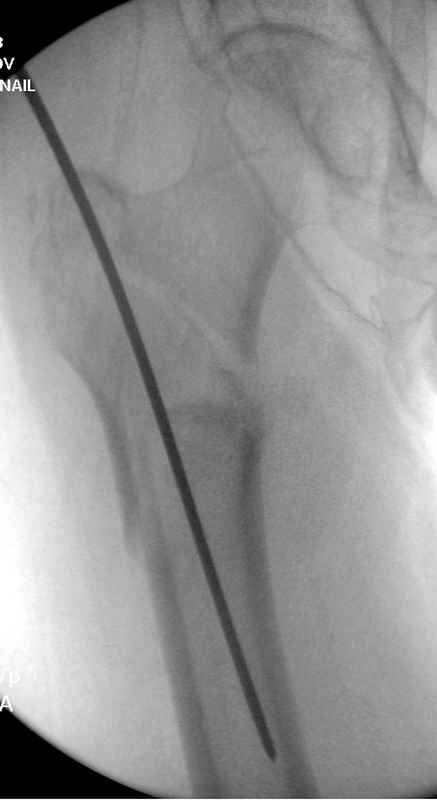

А вот к данным операциям без рентгена, как советует специалисты, я бы отнесся скептически, как раз здесь можно натворить много ошибок, например, от неправильной установки гвоздя мимо шейки до неудовлетворительной репозиции.

судя по картинкам с ЭОПа явно использовались приемы непрямой репозиции под его контролем, а так же интраоперационный ЭОП-контроль положения винтов, без такого контроля операция может ухудшить ситуацию (опять же учтите сроки) т.к. результат буде зависеть в большей степени от искусства хирурга, а не от технологии